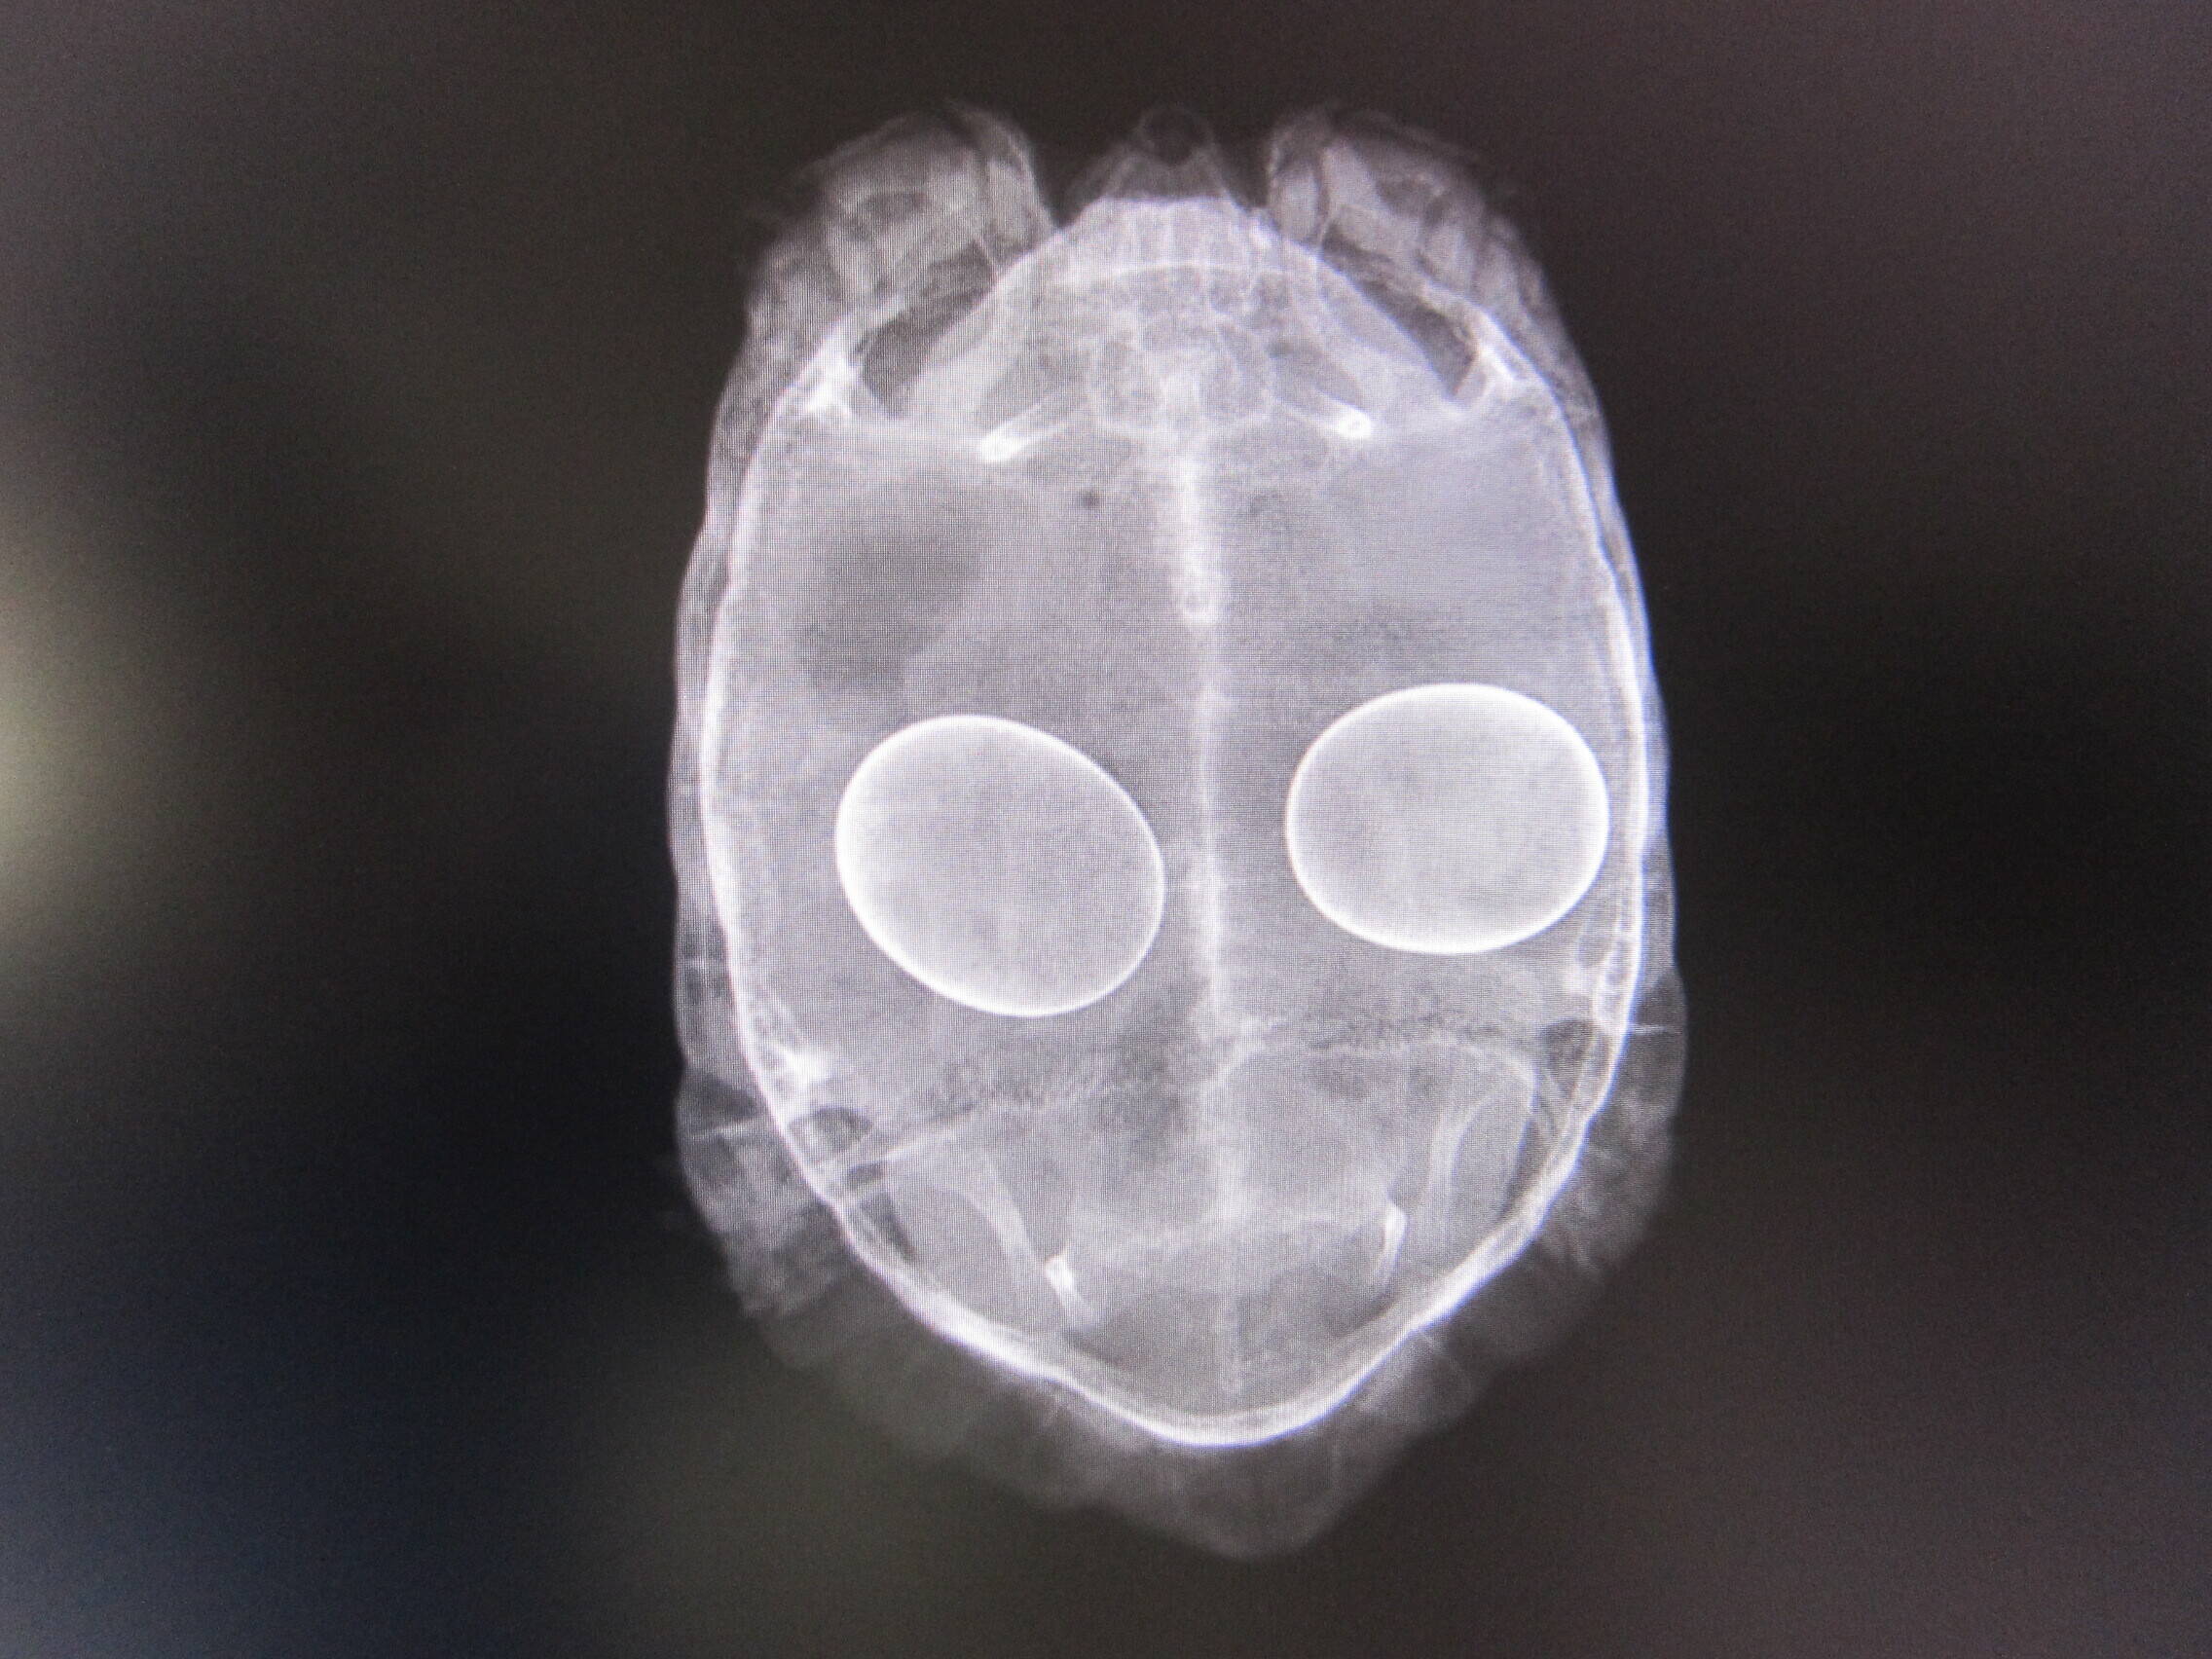

まずは、コチラ。

ウルトラマン!?

なわけなく、よーく見ると・・・

頭と手がありますね。もちろん足も。

そう、カメですよね!

どのカメかというと、コチラ。

はい、エジプトリクガメでした。

この個体は以前お腹に卵を持ったまま、ずっと産まなかったため、手術で卵を取り出したのです。

その後元気になり、現在も爬虫類館で展示されています。